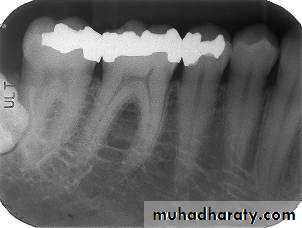

Bite-wing Radiography

• Indications:• Interproximal caries.

• Over-hang filling.

• Level of crestal bone between the teeth.

• Interproximal calculus.

• Principles:

• The film is placed in the mouth parallel to the crown of both upper & lower teeth.

• The film stabilized when the patient bites on the bite-wing tab or bite-wing film holder.

• The central ray of the x-ray beam is directed through the contacts of the teeth, using a +10 degree vertical angulation.

+10o vertical angulation is used to compensate for the slight bend of the upper portion of the film and the tilt of the maxillary teeth.